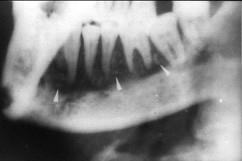

问题 慢性中央性颌骨骨髓炎的治疗应()

选项 A.及早拔除病灶牙 B.切开引流 C.死骨刮除、病灶牙拔除 D.大剂量抗生素控制感染 E.全身支持疗法

答案 C